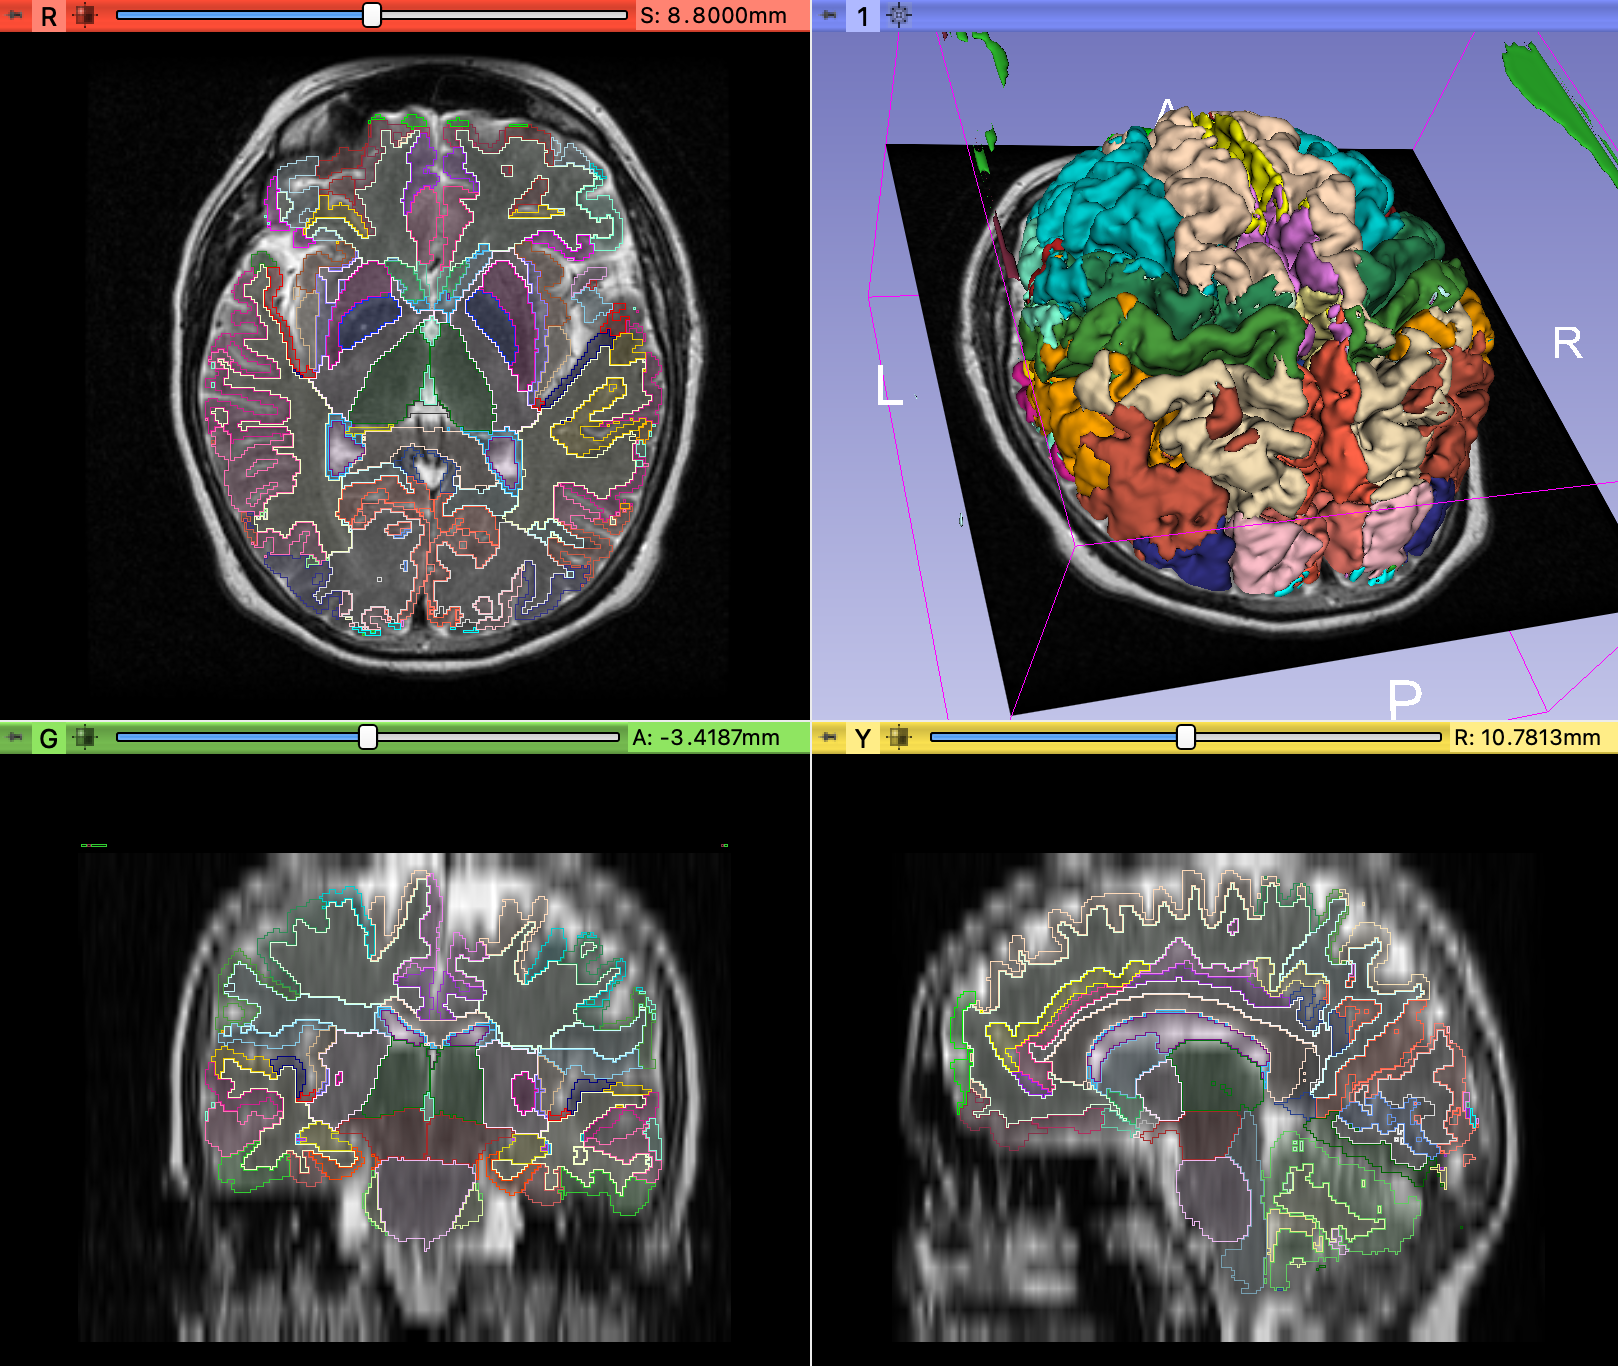

Parcellation run by @pieper on a synthetic 1 mm isotropic T1 MPRAGE generated from a 6.5 mm anisotropic T2 (using model from Iglesias et al. 2021):